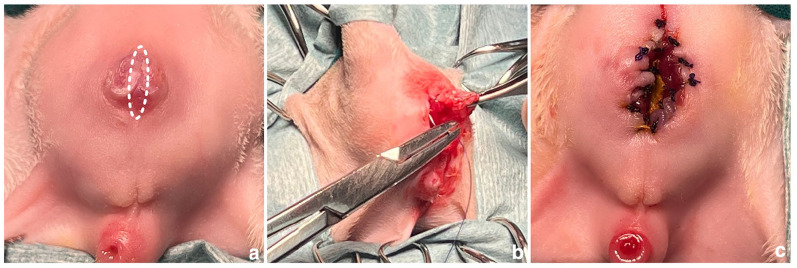

病例总结:一只2个月大的雄性英国短毛猫被怀疑患有肛门闭锁。体格检查发现肛门不穿孔,并有少量粪便通过阴茎排出。x线表现,连同逆行尿道造影,证实诊断为II型闭锁伴尿道直肠瘘。手术后患者恢复良好。8个月大时,先天性尿道直肠瘘经会阴单路手术治疗,包括经同一切口行瘘管切除术和去势。术后短期预后良好,排便和排尿正常。相关性和新信息:闭锁是一种罕见的先天性异常,特别是在公猫。尽管手术技术取得了进步,但该病例是首例成功分阶段手术治疗雄性小猫II型闭锁尿道直肠瘘的病例,可能影响未来类似先天性异常的手术入路。

Case summary: A 2-month-old male British Shorthair cat was referred with suspected atresia ani. Physical examination revealed an imperforate anus and dribbling of faecal discharge through the penis. Radiographic findings, along with a retrograde urethrogram, confirmed the diagnosis of type II atresia ani with a urethrorectal fistula. Surgical anoplasty was performed and the patient recovered well. At 8 months of age, surgical treatment for the congenital urethrorectal fistula was carried out via a single perineal approach, including fistulectomy and castration through the same incision. Postoperative short-term outcomes were excellent, with normal defecation and urination.